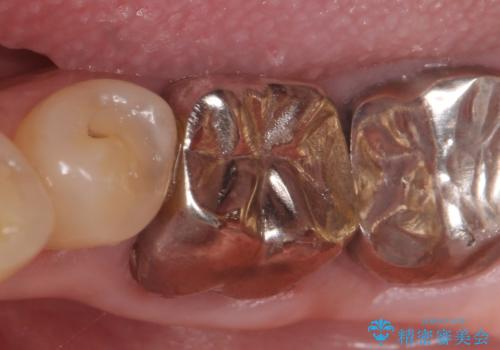

- 左下の銀歯が外れたので診て欲しいといらっしゃった方の症例です。

他院にて再装着したが不安なので、根管治療からやり直したいとのことでした。

再根管治療終了後、オールセラミッククラウンによる補綴を行いました。